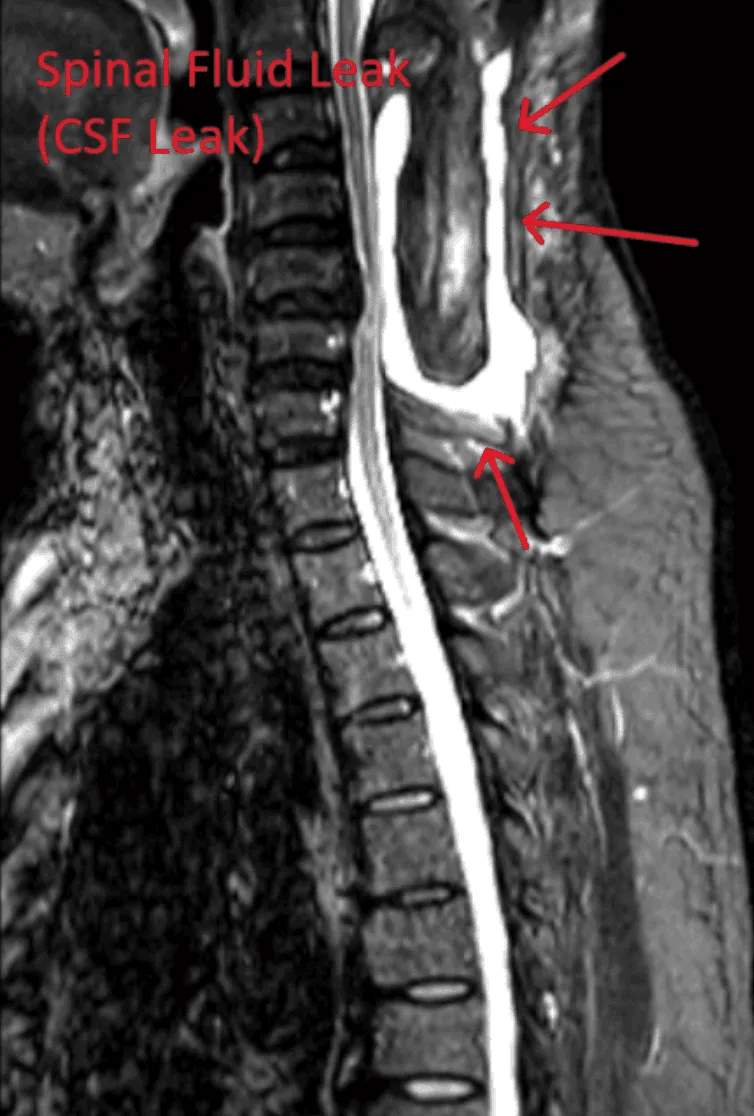

MRI scan of a spine showing a cerebrospinal fluid leak, highlighted with red arrows.

Spinal Fluid Leak

Dural puncture from the needle causes cerebrospinal fluid leaks, leading to severe headaches and potential complications.